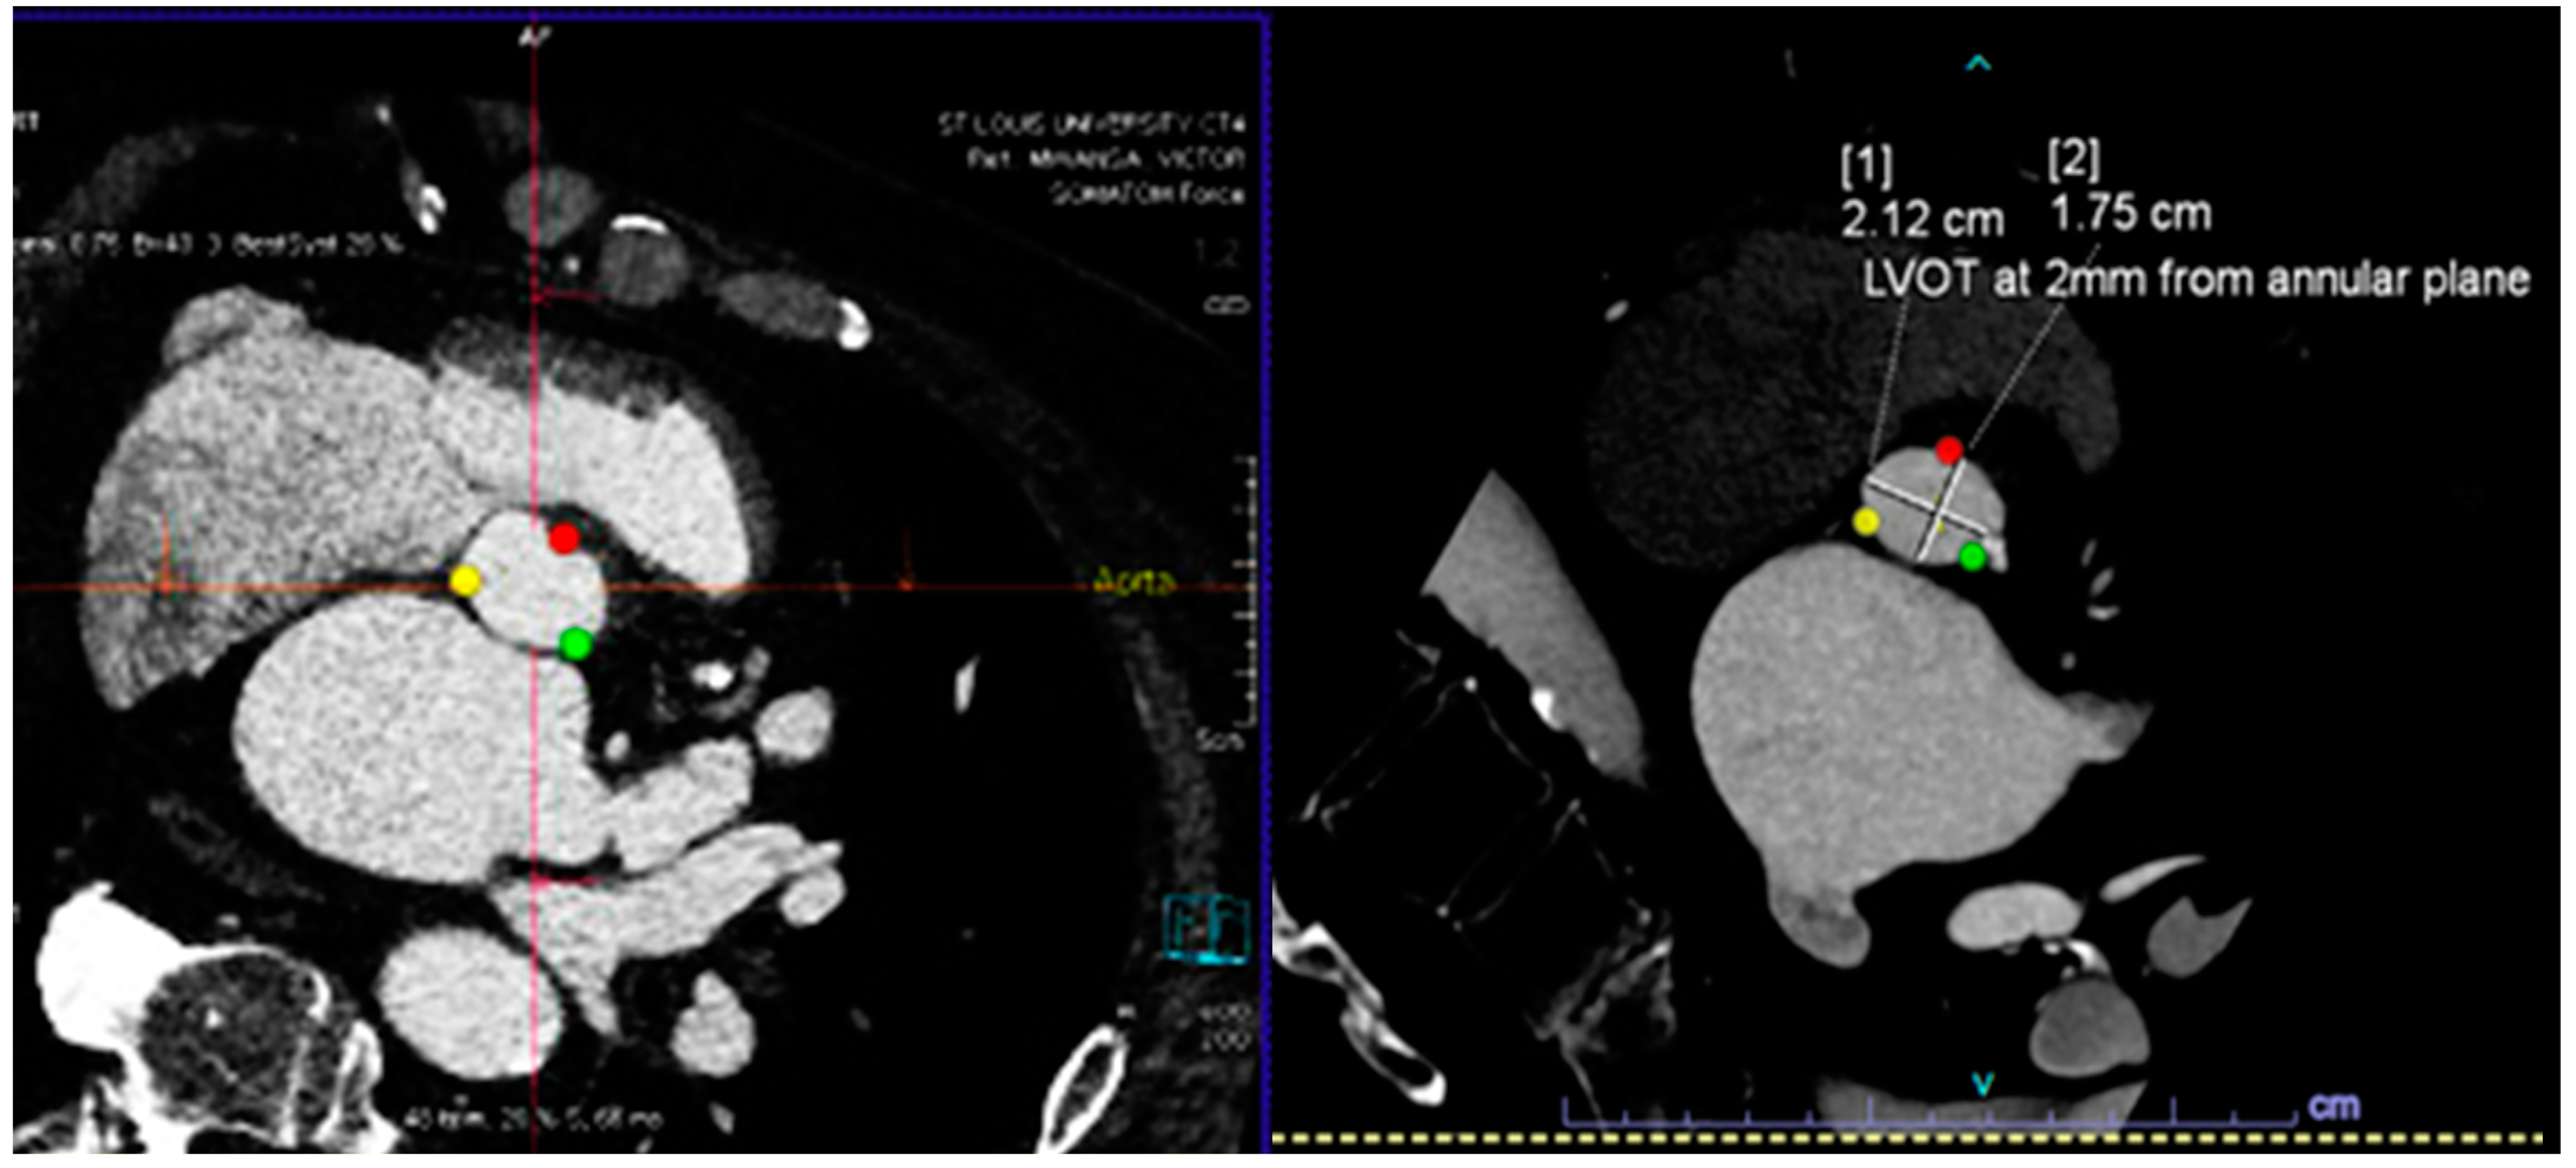

| Santaló-Corcoy [20] | 200 CTs (35 for training, and 17 for testing) | Manual CT measurement by an expert cardiologist using 3Mensio. | Correlation between manual and automated measurements | DL algorithms (MeshDeformNet) for landmark detection followed by segmentation | mean absolute relative error was within 5% for most measurements, except for coronary height (11.6% and 16.5%). |

| Theriault-Lauzier [21] | 94 CTs of severe AS (K-fold cross-validation with K=) | Manually segmented AV annulus | Correlation between manual and automated measurements | recursive multiresolution CNN for localization of the AV annulus centroid | average out-of-plane localization error of 0.9 ± 0.8 mm for the evaluation dataset. The proposed algorithm is on par with automated methods for localization and approaches in providing an expert-level accuracy. |

- Santaló-Corcoy, M.; Corbin, D.; Tastet, O.; Lesage, F.; Modine, T.; Asgar, A.; Ben Ali, W. TAVI-PREP: A Deep Learning-Based Tool for Automated Measurements Extraction in TAVI Planning. Diagnostics 2023, 13, 3181. [Google Scholar] [CrossRef]